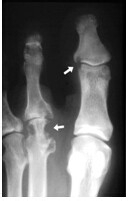

5、五:痛风的影像学检查一X线表现。